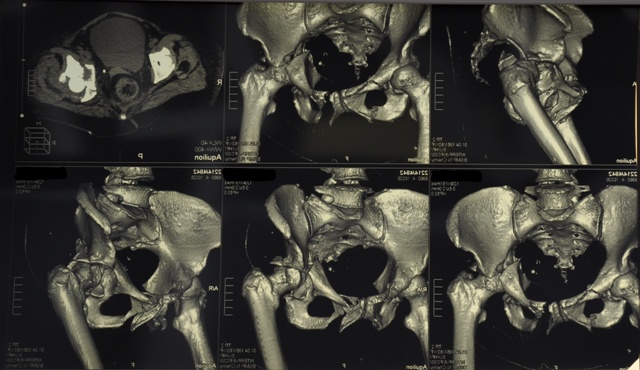

Пациентка  получила травму в результате ДТП, находясь внутри автомобиля. Травма получена 20.04.2011г. Сразу после травмы доставлена в Менделеевскую ЦРБ с диагнозом: Сочетанная травма. Множественные закрытые многооскольчатые переломы лонной, седалищной и подвздошной костей справа и слева, оскольчатый перелом дна и крыши вертлужной впадины слева с вывихом бедра. Закрытый перелом 8-10 ребер слева. Травматический шок 3-4 ст.

06.04.2011г. произведена операция остеосинтеза подвздошной и седалищной кости слева, остеосинтез заднего края и крыши вертлужной впадины,   тотальное бесцементное эндопротезирование левого тазобедренного сустава.

- Из переднего пахово-подвздошного доступа произведен остеосинтез  реконструктивной пластиной подвздошной и седалищной костей с  репозицияей  и фиксацией передней

коллоны вертлужной впадины.

- Из заднего доступа произведена репозиция и фиксация крыши и заднего края вертлужной впадины реконструктивной пластиной, а так же тотальное бесцементное эндопротезирование тазобедренного сустава.Между «вкладышем» чашки вертлужного компонента и самой вертлужной впадиной использован аутотрансплант из костной стружки. Была так же произведена ревизия седалищного нерва – нарушения целостности нерва не выявленно.